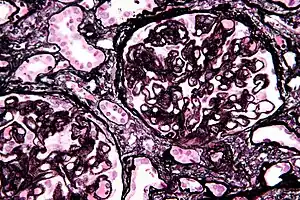

| Micrograph of diffuse proliferative lupus nephritis showing increased mesangial matrix and mesangial hypercellularity. Kidney biopsy. PAS stain. | |

Class II disease (mesangial proliferative glomerulonephritis) is noted by mesangial hypercellularity and matrix expansion. Microscopic haematuria with or without proteinuria may be seen. Hypertension, nephrotic syndrome, and acute kidney injury are very rare at this stage.[14]